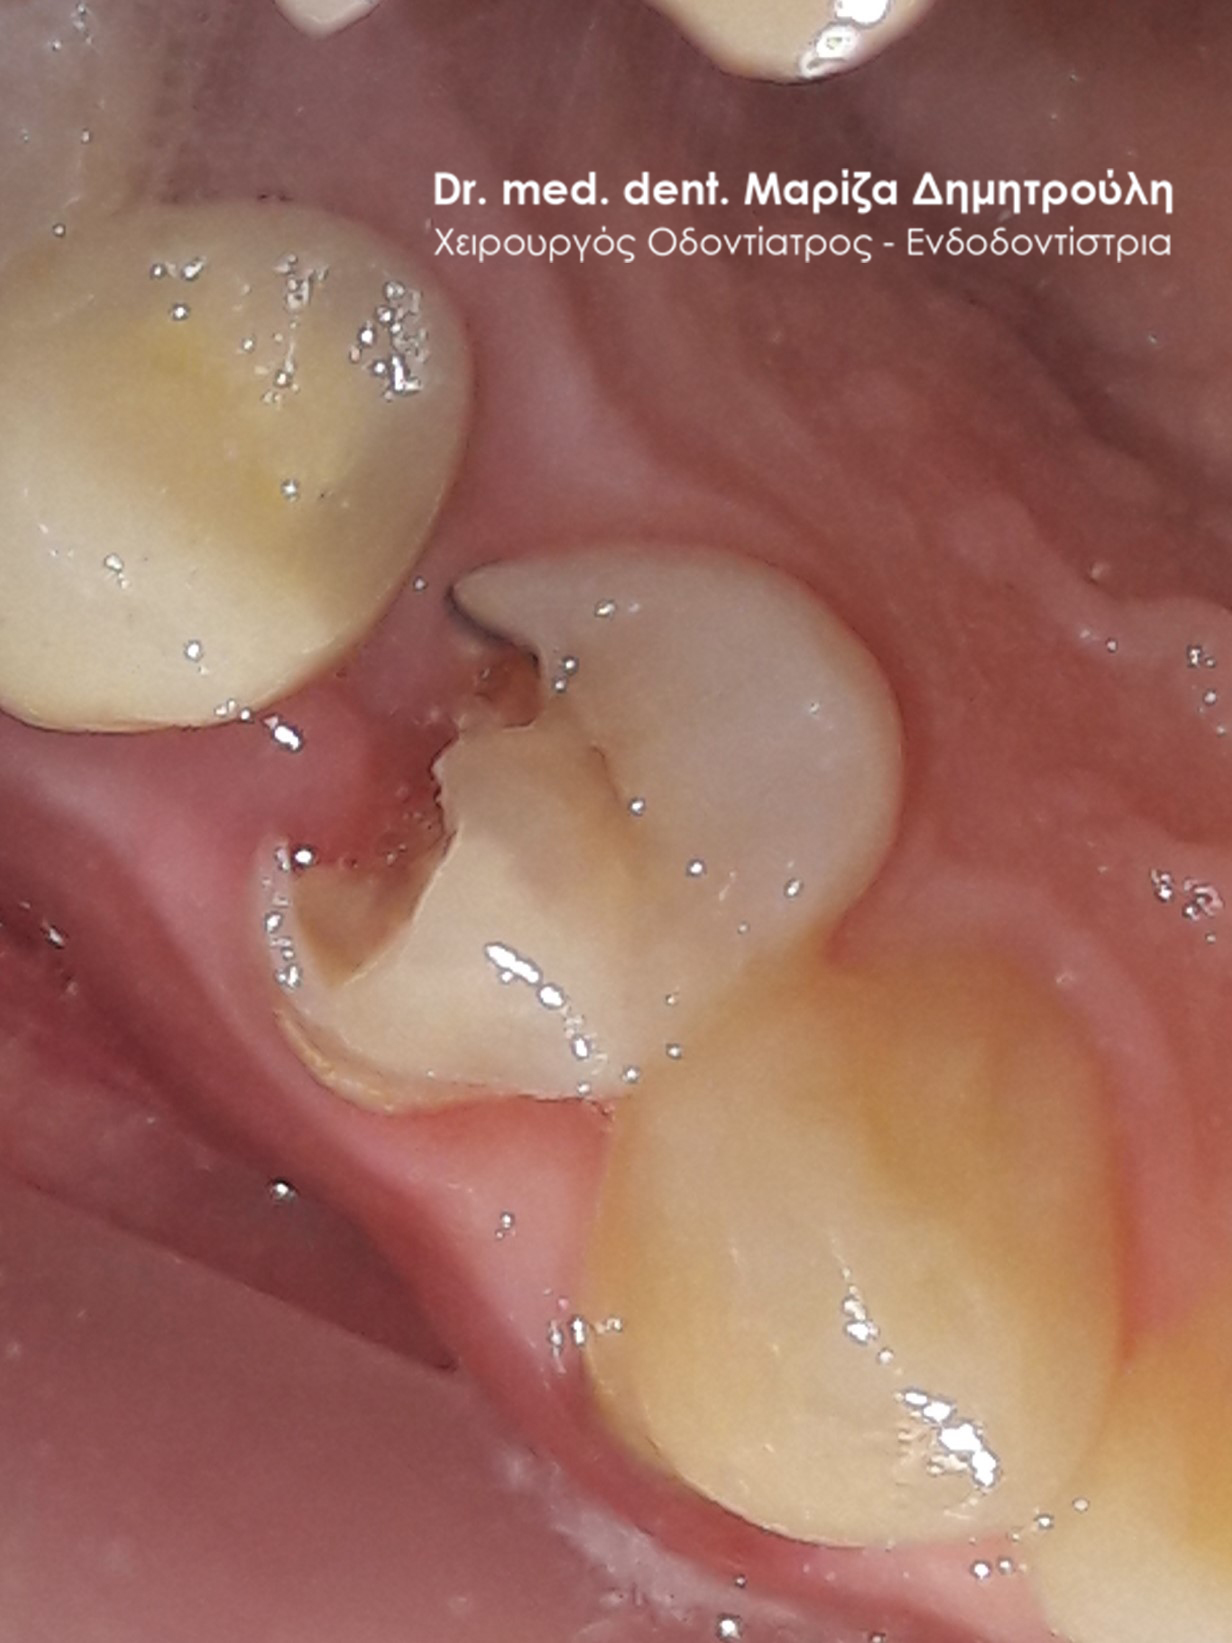

Περιστατικό – Σφράγισμα δοντιού

Η ασθενής επισκέφτηκε το ιατρείο ως επείγον περιστατικό με την επιθυμία της άμεσης και γρήγορης αποκατάστασης του σπασμένου δοντιού της που την πονούσε. Υπό τις προαναφερθέντες συνθήκες η θεραπεία επιλογής ήταν η ανασύσταση του δοντιού λευκό σφράγισμα σύνθετης ρητίνης. Η θεραπεία ολοκληρώθηκε εντός 20 λεπτών και η ασθενής μπορούσε να επιστρέψει άμεσα στη δουλειά της.

ΠΡΙΝ

META